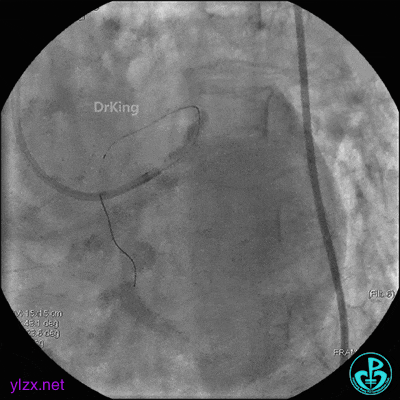

1周后复查造影,见粗大前降支3级血流,近端严重狭窄伴管壁严重钙化影,病变累及前降支开口。

球囊扩张后前降支中段植入支架。

前降支近端串联植入支架,前降支开口支架精确定位。

支架内非顺应性球囊后扩张。